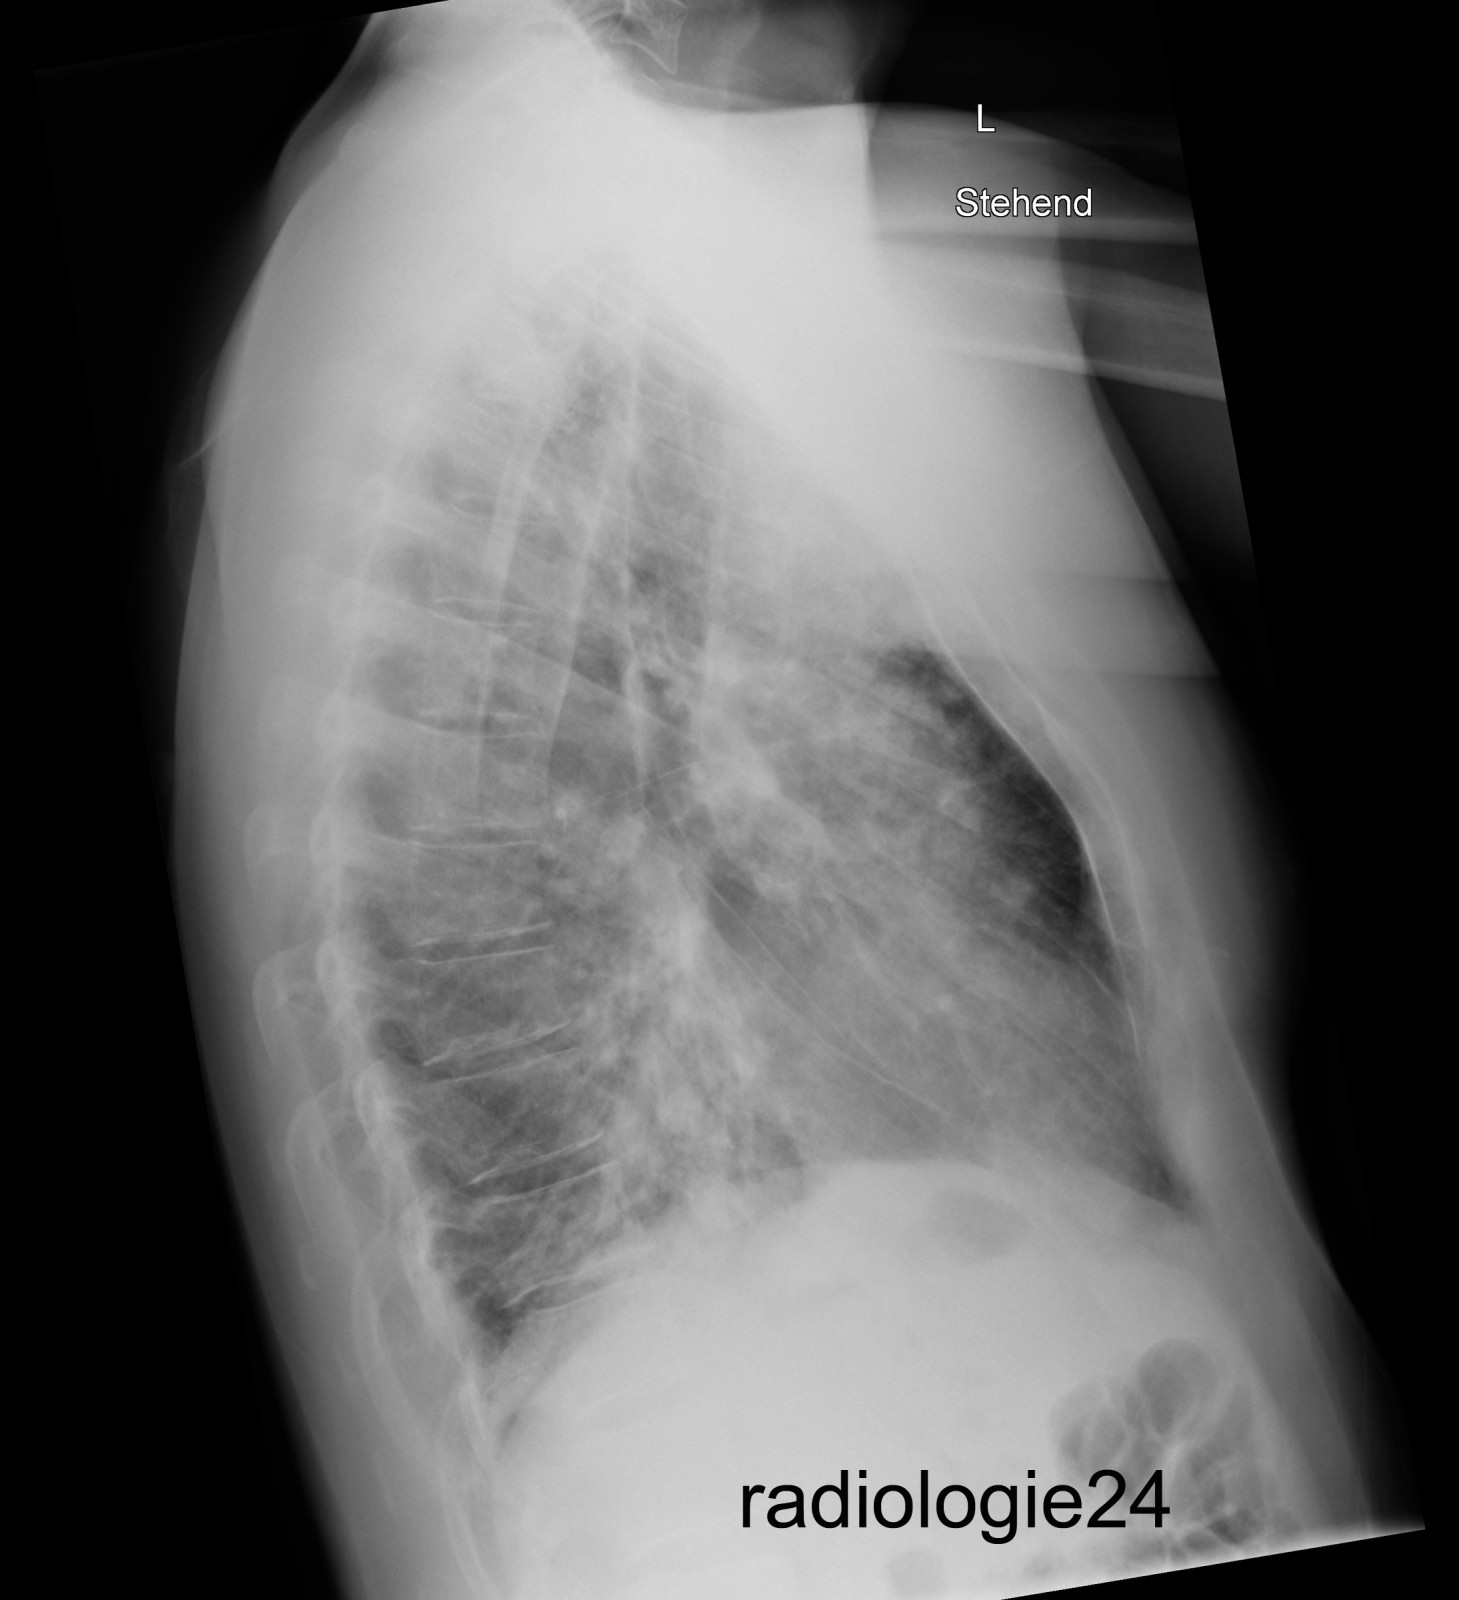

Röntgenfall des Monats August 2018 mit Auflösung

40 jähriger Patient

Triathlon Sportler.

Bei einem Wettkampf muss der Patient wegen akut auftretender Dyspnoe nach dem Schwimmen, die Disziplin des Fahrradfahrens abbrechen und kann den Triathlon nicht beenden.

Einlieferung in die Notaufnahme des nächstliegenden Spital.

Ihre Diagnose?

Weitere radiologische Diagnostik notwendig?